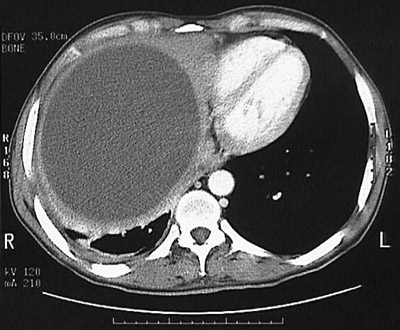

The

large cyst

seen here is the result of

Echinococcus granulosus

. The size of the cyst produces the projection of the right liver lobe high into the chest to the level of the

ventricles of the heart

.